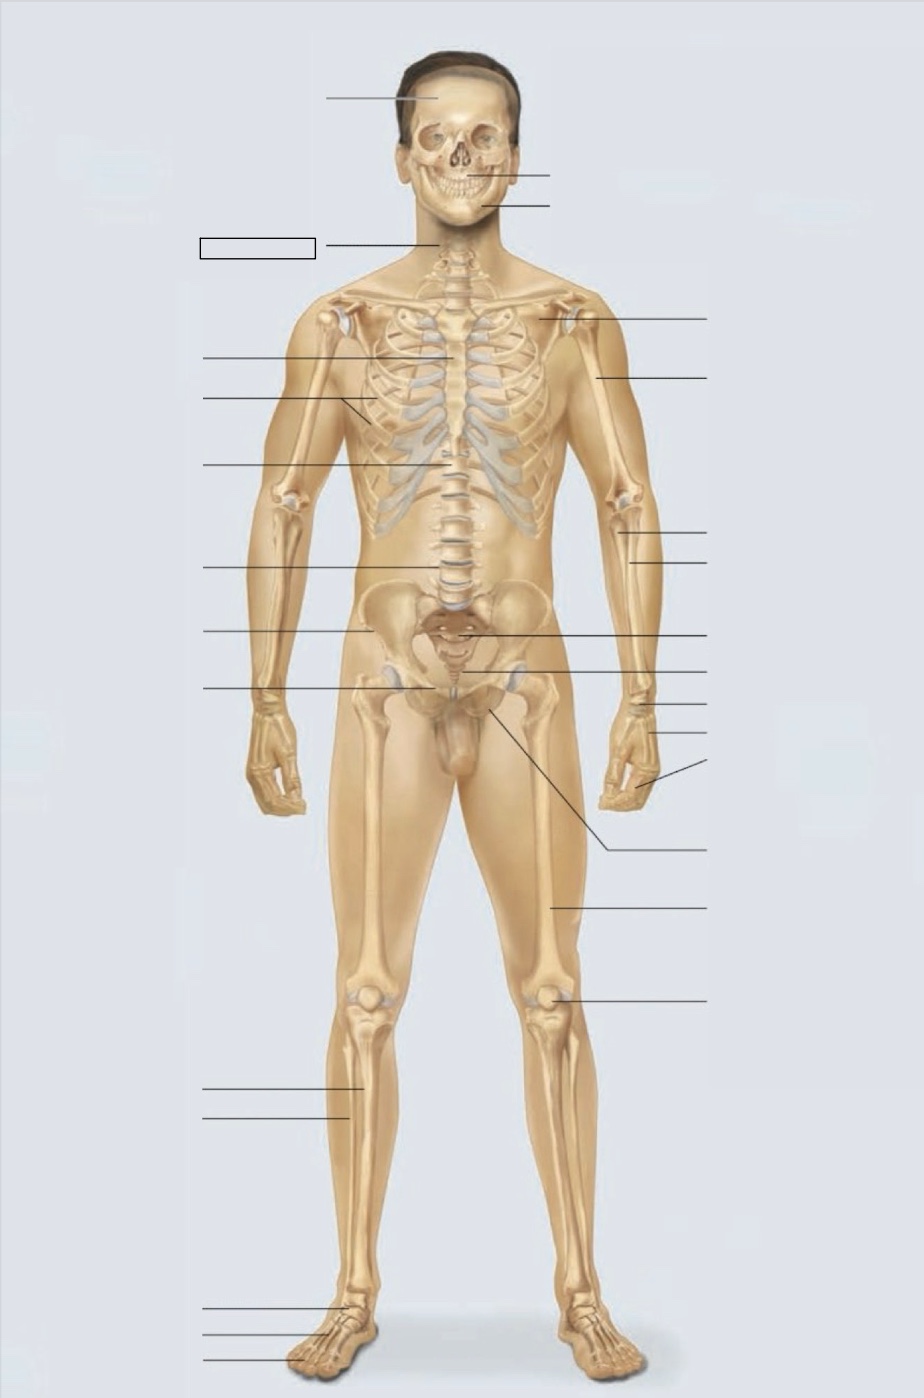

maxilla

mandible

scapula

humerus

ulna

radius

sacrum

coccyx

carpals

metacarpals

phalanges

ischium

femur

patella

phalanges

metatarsals

tarsals

fibula

tibia

pubis

ilium

lumbar vertebrae (L4)

thoracic vertebrae (T11)

ribs

sternum

cervical vertebrae

skull